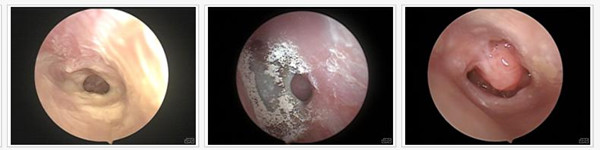

诊断中耳炎一定要“准”,因为,中耳炎长时间不得到有效治疗的话引发耳膜穿孔,严重时还会导致耳聋,必须对其高度重视。除了耳朵流脓、中耳炎的常见症状有哪些?西安新城中大耳鼻喉医院耳科冯...[详细]

据调查显示,上个世纪大部分耳膜穿孔患者在治疗之前,往往会很犹豫,主要担心治疗效果、治疗费用、医生经验等。而近年来,自体脂肪压片鼓膜修补技术的应用,治疗成功率极大幅度提高,耳膜穿孔...[详细]

简单地说,胆脂瘤型中耳炎是慢性化脓性中耳炎的一种常见类型。众所周知慢性化脓性中耳炎可分为三种类型:单纯型、骨疡型、胆脂瘤型。其中以胆脂瘤型的后果最为严重。[详细]